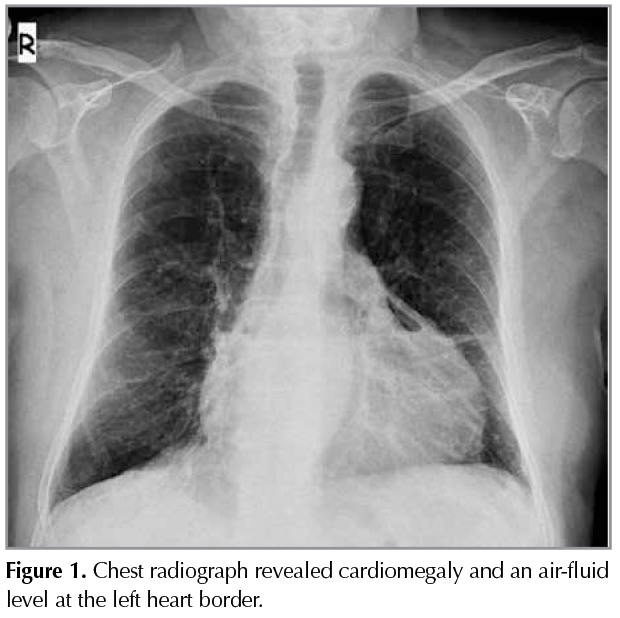

A 69-year-old man was admitted for fever and dyspnea associated with productive cough, sputum. He had COPD for five years and was using inhaled bronchodilators. He had a history of 45 pack-year smoking. Also he had hypothyroidism, he was using levothyroxine but he had for gotten to take the drug for two weeks. On admission, his temperature was 38.3?C, with a respiratory rate of 28 breaths perminute, a pulse of 100 beats perminute, and a blood pressure of 110/70 mmHg. Breathing sounds were decreased bilaterally. The complete blood cell count on admission revealed a white blood cell count of 18.770/mm3 (neutrophils, 85.7%; lymphocytes, 9.5%; monocytes, 4.6%; eosinophils, 0.1%; basophils, 0.1%), hemoglobin level of 12.0 g/dL, platelet count of 195.000/mm3, and T3: 0.42 ng/mL, T4: 3.06 ng/mL, TSH: 20.43 IU/mL. C-reactive protein and procalcitonin was markedly elevated to 292 mg/L and 0.9 ng/mL respectively. His anteroposterior chest radiograph revealed cardiomegaly and we observed an air-fluid level at the left heart border (Figure 1). Computed tomography (CT) showed? 2 cm pericardial effusion and air in the pericardial space (Figure 2). There was no evidence of pneumomediastinum. Echocardiogram showed a mild pericardial effusion with no echocardiographic evidence of cardiac tamponade. The patient was man aged conservatively with antibiotics, bronchodilators and he was started on levothyroxine treatment and, subsequently, clinical symptoms, pericardial effusion and air in the pericardial spacere solved with the treatment.

Figure 1

Pneumopericardium can be diagnosed by conventional chest radiography, CT, or echocardiography (8). We noticed an air-fluid level on chest graph of our patient and after that confirmed by CT.